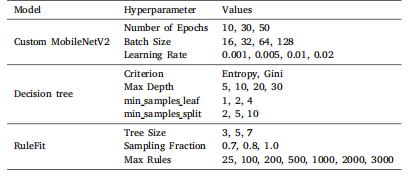

This section introduces information about the experiments performed and the results produced in this study. This section also prvides additional information about the datasets, experimental setup,optimized hyper-parameters, and evaluation metrics used in this study.

本节介绍本研究中开展的实验及其产生的结果,还提供了关于本研究中使用的数据集、实验设置、优化的超参数和评估指标的额外信息。

Table 2Hyperparameters values for each model used in grid search optimization

表2 网格搜索优化中所用各模型的超参数值。